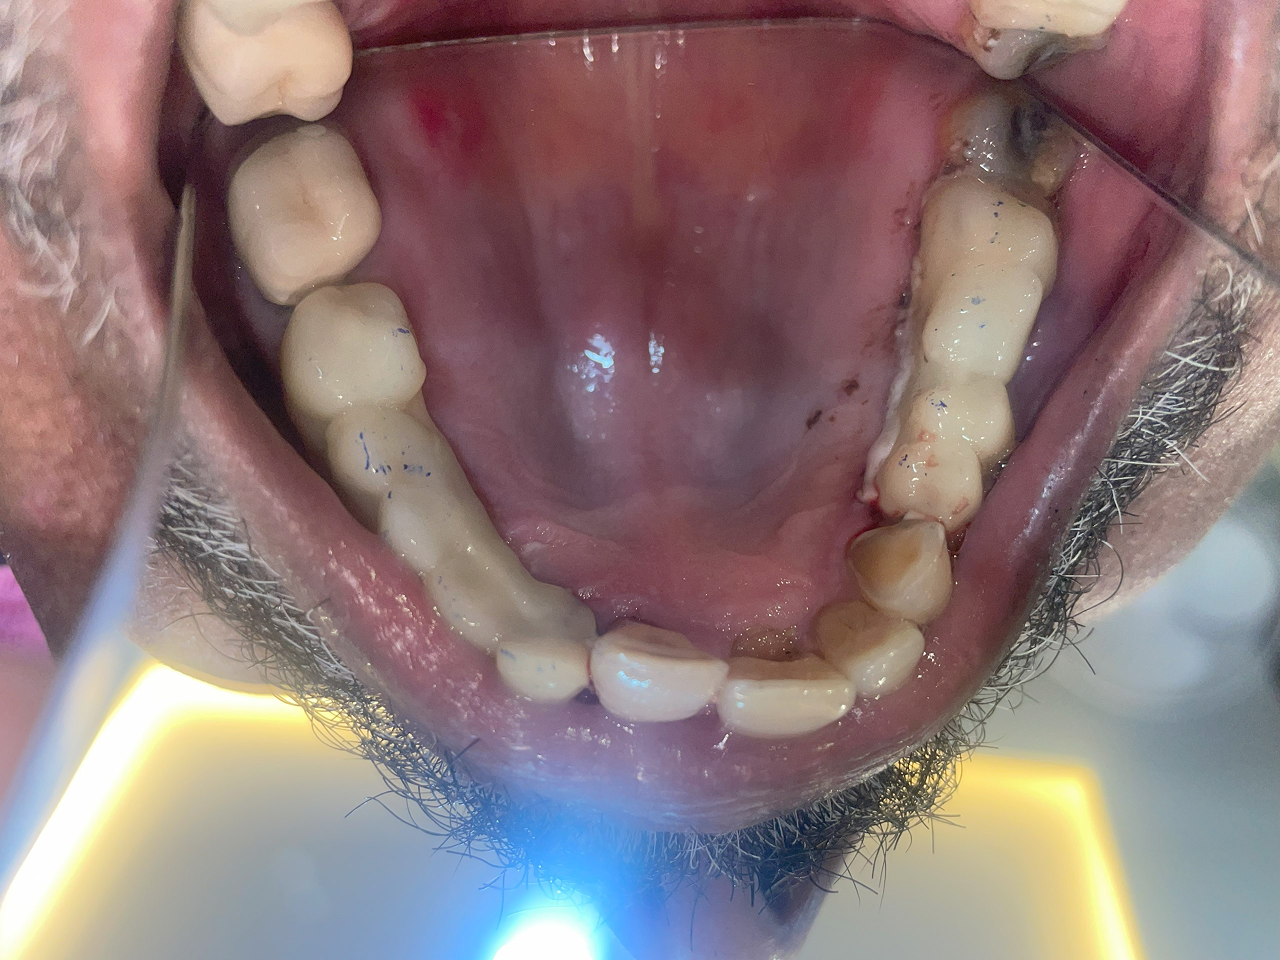

Full Mouth Rehabilitation

This includes comprehensive dental work such as implants, crowns, root canals, and other restorations to fully restore dental health and aesthetics.

Before treatment